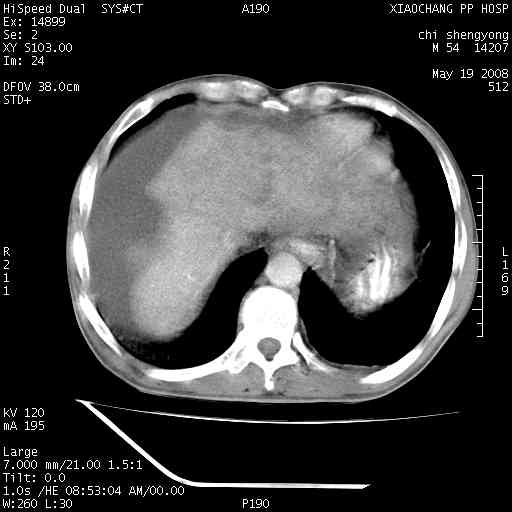

以下是引用zjzjr在2008-5-21 10:52:00的发言:[br]肝左叶巨块型肝癌伴门静脉左支瘤栓形成.肝硬化、腹水,胃底静脉曲张,脾术后改变。

以下是引用随光逐影在2008-5-21 16:20:00的发言:[br]1)肝左叶肝癌伴门静脉左支瘤栓形成,腹膜后淋巴结转移。2)肝硬化、腹水、胃底静脉曲张。3)胆囊炎。4)脾脏缺如,为切除术后所致。